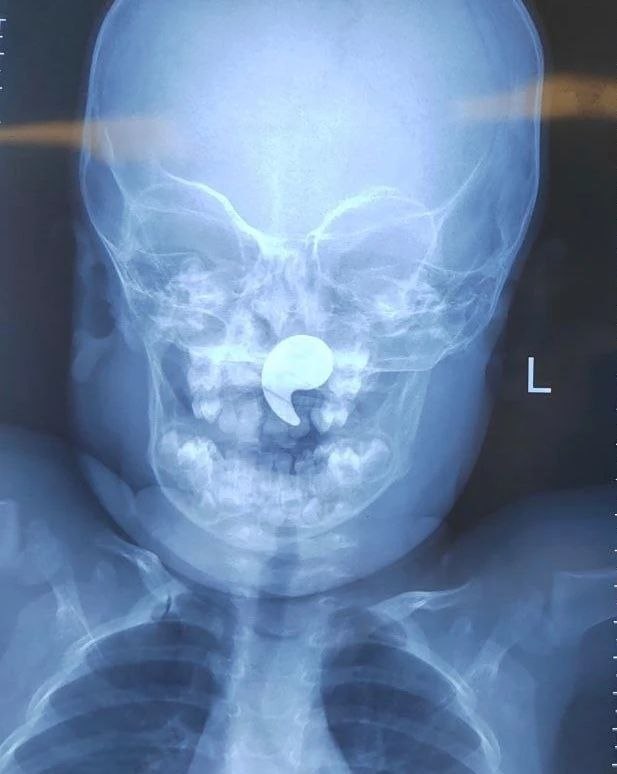

Мама сказала, что девочка играла с магнитом в форме запятой и подавилась им.

Магнит сместился в носоглотку.